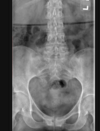

Cisto ósseo aneurismático

Acomete paciente jovem (fise aberta);

Localização excêntrica, aspecto em favo de mel no RX;

Pode ter reforço periosteal;

RM:lesão multicística; Septos + nível liquido-liquido (lesões dx diferencial: COS fraturado, COA, TCG ou osteossarcoma telangiectásico).

Primário ou Secundário à outros tumores: TCG, DF, Condroblastoma.